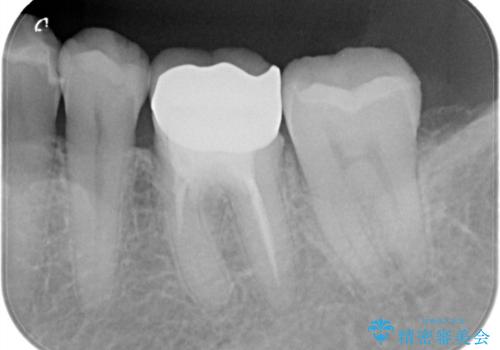

拡大鏡下で丁寧に虫歯を取り除き、セラミックインレーによる修復治療を行いました。

銀歯を固着するセメントは経年劣化し溶け、隙間ができます。そこにプラークが侵入して虫歯が再発します。今回のように銀歯が脱離してしまうこともあります。

今回は銀歯が取れたので、虫歯が神経まで達して痛みが出る前に、強度・審美に優れ、虫歯の再発の少ないセラミックインレーにて治療を行うことができました。